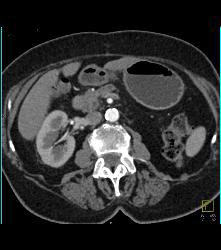

Carcinoma of the Pancreatic Head With Dilated Pancreatic Duct